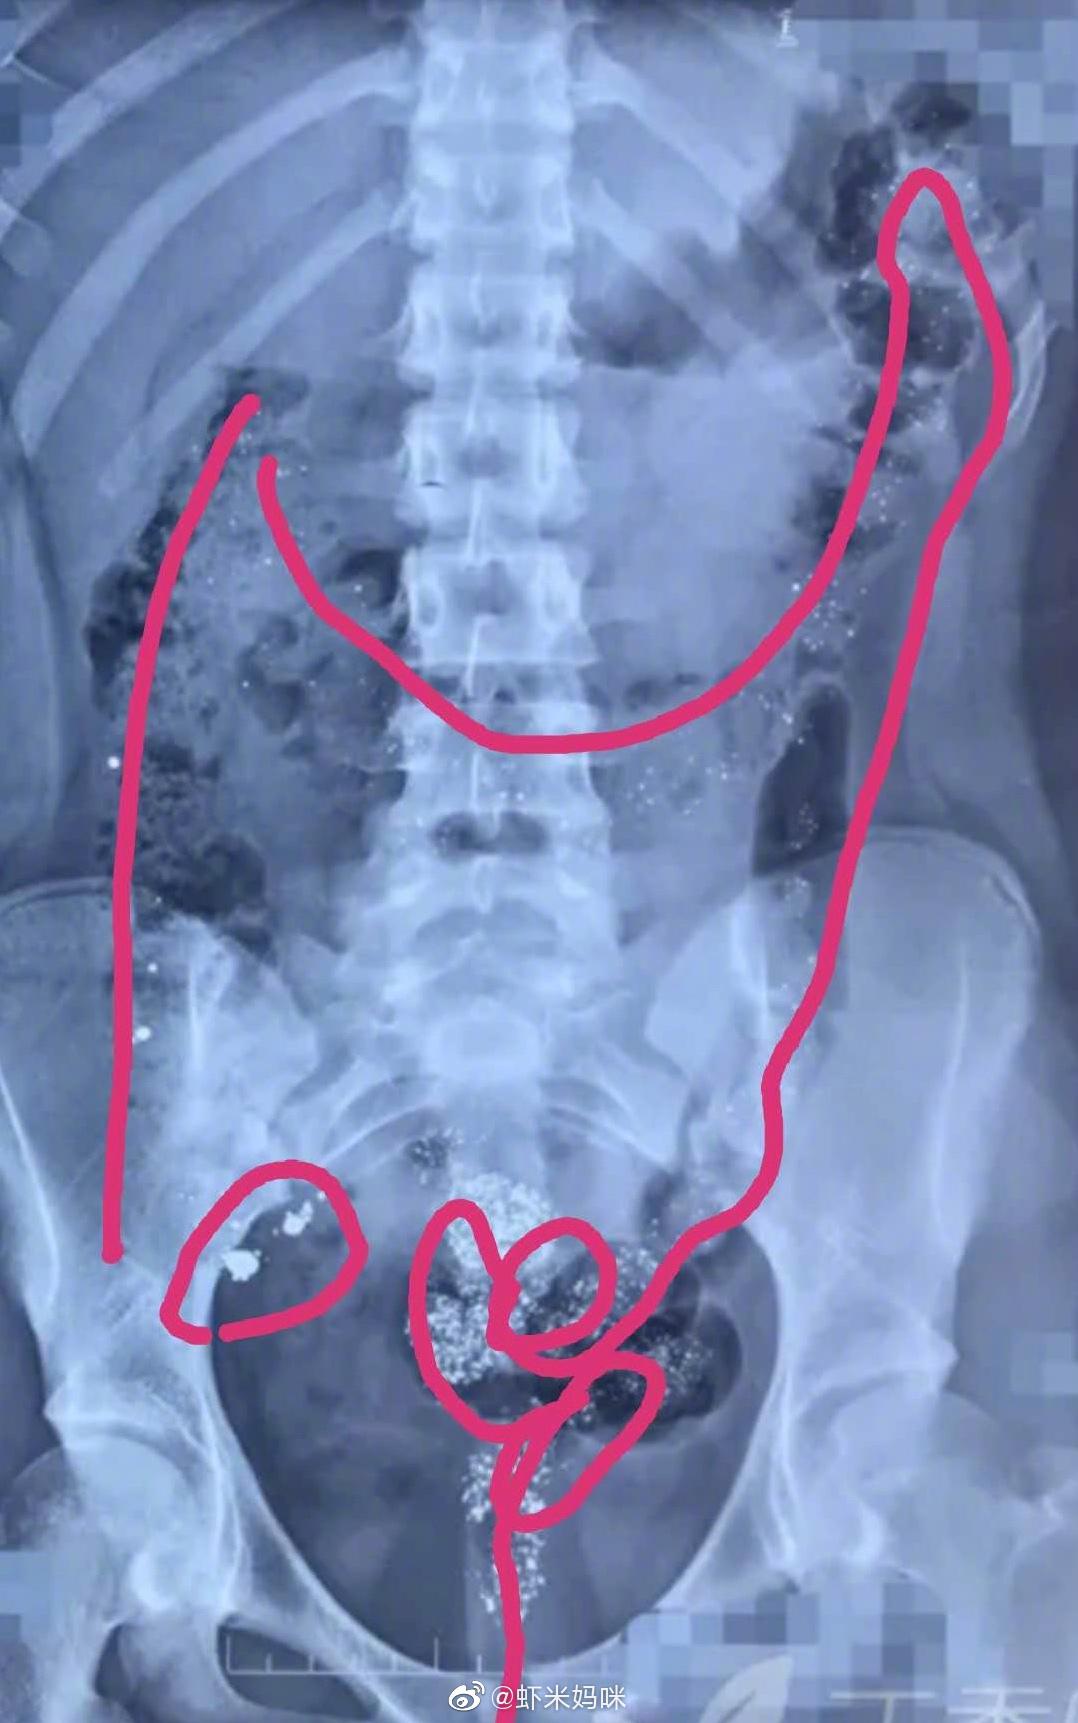

【13岁女孩打碎17支水银体温计喝下 引发的儿童汞中毒案例讨论】前几天,我的同门群里热烈讨论一个案例,13 岁女孩,自行打碎 17 支水银体温计,将其中的水银倒入矿泉水瓶里全部喝下。

如图:右下腹是阑尾,少量水银掉进阑尾里去了。

如果消化道没有炎症也没有溃疡,保护胃肠道粘膜,大部分的水银会在3—5天内排出体外,少量掉进阑尾的水银,需要2到3周的时间慢慢排出。可以通过体位调整,垫高右下腹的方式促进阑尾里的水银排出。可能有血汞、尿汞一过性升高,总体应该预后良好。